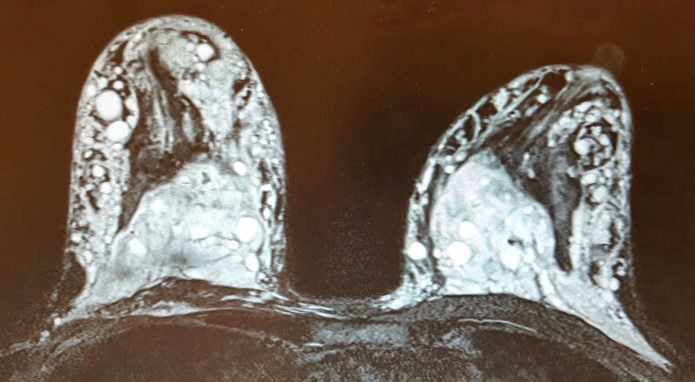

MRI payudara menunjukkan beberapa gelembung putih karena injeksi silikon untuk peningkatan payudara (bukan pengobatan yang disetujui FDA)